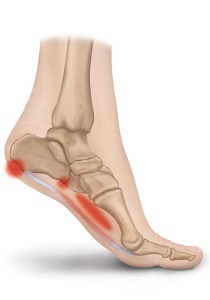

Plantar Fasciitis is an inflammation caused by excessive stretching of the plantar fascia. The plantar fascia is a broad band of fibrous tissue, which runs along the bottom surface of the foot, attaching at the bottom of the heel bone and extending to the forefoot. When the plantar fascia is excessively stretched, this can cause plantar fasciitis, which can also lead to heel pain, arch pain, and heel spurs.

Plantar Fasciitis often leads to heel pain, heel spurs, and/or arch pain. The excessive stretching of the plantar fascia that leads to the inflammation and discomfort can be caused by the following: Over-pronation (flat feet) which results in the arch collapsing upon weight bearing; A foot with an unusually high arch; A sudden increase in physical activity; Excessive weight on the foot, usually attributed to obesity or pregnancy; or Improperly fitting footwear. Over-pronation (flat feet) is the leading cause of plantar fasciitis. Over-pronation occurs in the walking process, when a person’s arch collapses upon weight bearing, causing the plantar fascia to be stretched away from the heel bone. With Plantar Fasciitis, the bottom of your foot usually hurts near the inside of the foot where the heel and arch meet. The pain is often acute either first thing in the morning or after a long rest, because while resting the plantar fascia contracts back to its original shape. As the day progresses and the plantar fascia continues to be stretched, the pain often subsides.

The key for the proper treatment of plantar fasciitis is determining what is causing the excessive stretching of the plantar fascia. When the cause is over-pronation (flat feet), an orthotic with rearfoot posting and longitudinal arch support is an effective device to reduce the over-pronation and allow the condition to heal. If you have unusually high arches, which can also lead to plantar fasciitis, cushion the heel, absorb shock and wear proper footwear that will accommodate and comfort the foot. Other common treatments include stretching exercises, plantar fasciitis night splints, wearing shoes that have a cushioned heel to absorb shock, and elevating the heel with the use of a heel cradle or heel cup. Heel cradles and heel cups provide extra comfort, cushion the heel, and reduce the amount of shock and shear forces placed during everyday activities. Every time your foot strikes the ground, the plantar fascia is stretched. You can reduce the strain and stress on the plantar fascia by following these simple instructions: Avoid running on hard or uneven ground, lose any excess weight and wear shoes and orthotics that support your arch to prevent over-stretching of the plantar fascia.

The heel bone is the largest bone in the foot and absorbs the most amount of shock and pressure. A heel spur develops as an abnormal growth of the heel bone. Calcium deposits form when the plantar fascia pulls away from the heel area, causing a bony protrusion, or heel spur to develop. The plantar fascia is a broad band of fibrous tissue located along the bottom surface of the foot that runs from the heel to the forefoot. Heel spurs can cause extreme pain in the rearfoot, especially while standing or walking.

Heel spurs develop as an abnormal growth in the heel bone due to calcium deposits that form when the plantar fascia pulls away from the heel. This stretching of the plantar fascia is usually the result of over-pronation (flat feet), but people with unusually high arches (pes cavus) can also develop heel spurs. Women have a significantly higher incidence of heel spurs due to the types of footwear often worn on a regular basis.

The key for the proper treatment of heel spurs is determining what is causing the excessive stretching of the plantar fascia. When the cause is over-pronation (flat feet), an orthotic with rearfoot posting and longitudinal arch support is an effective device to reduce the over-pronation, and allow the condition to heal. Other common treatments include stretching exercises, losing weight, wearing shoes that have a cushioned heel that absorbs shock, and elevating the heel with the use of a heel cradle, heel cup, or orthotic. Heel cradles and heel cups provide extra comfort and cushion to the heel, and reduce the amount of shock and shear forces experienced from everyday activities.